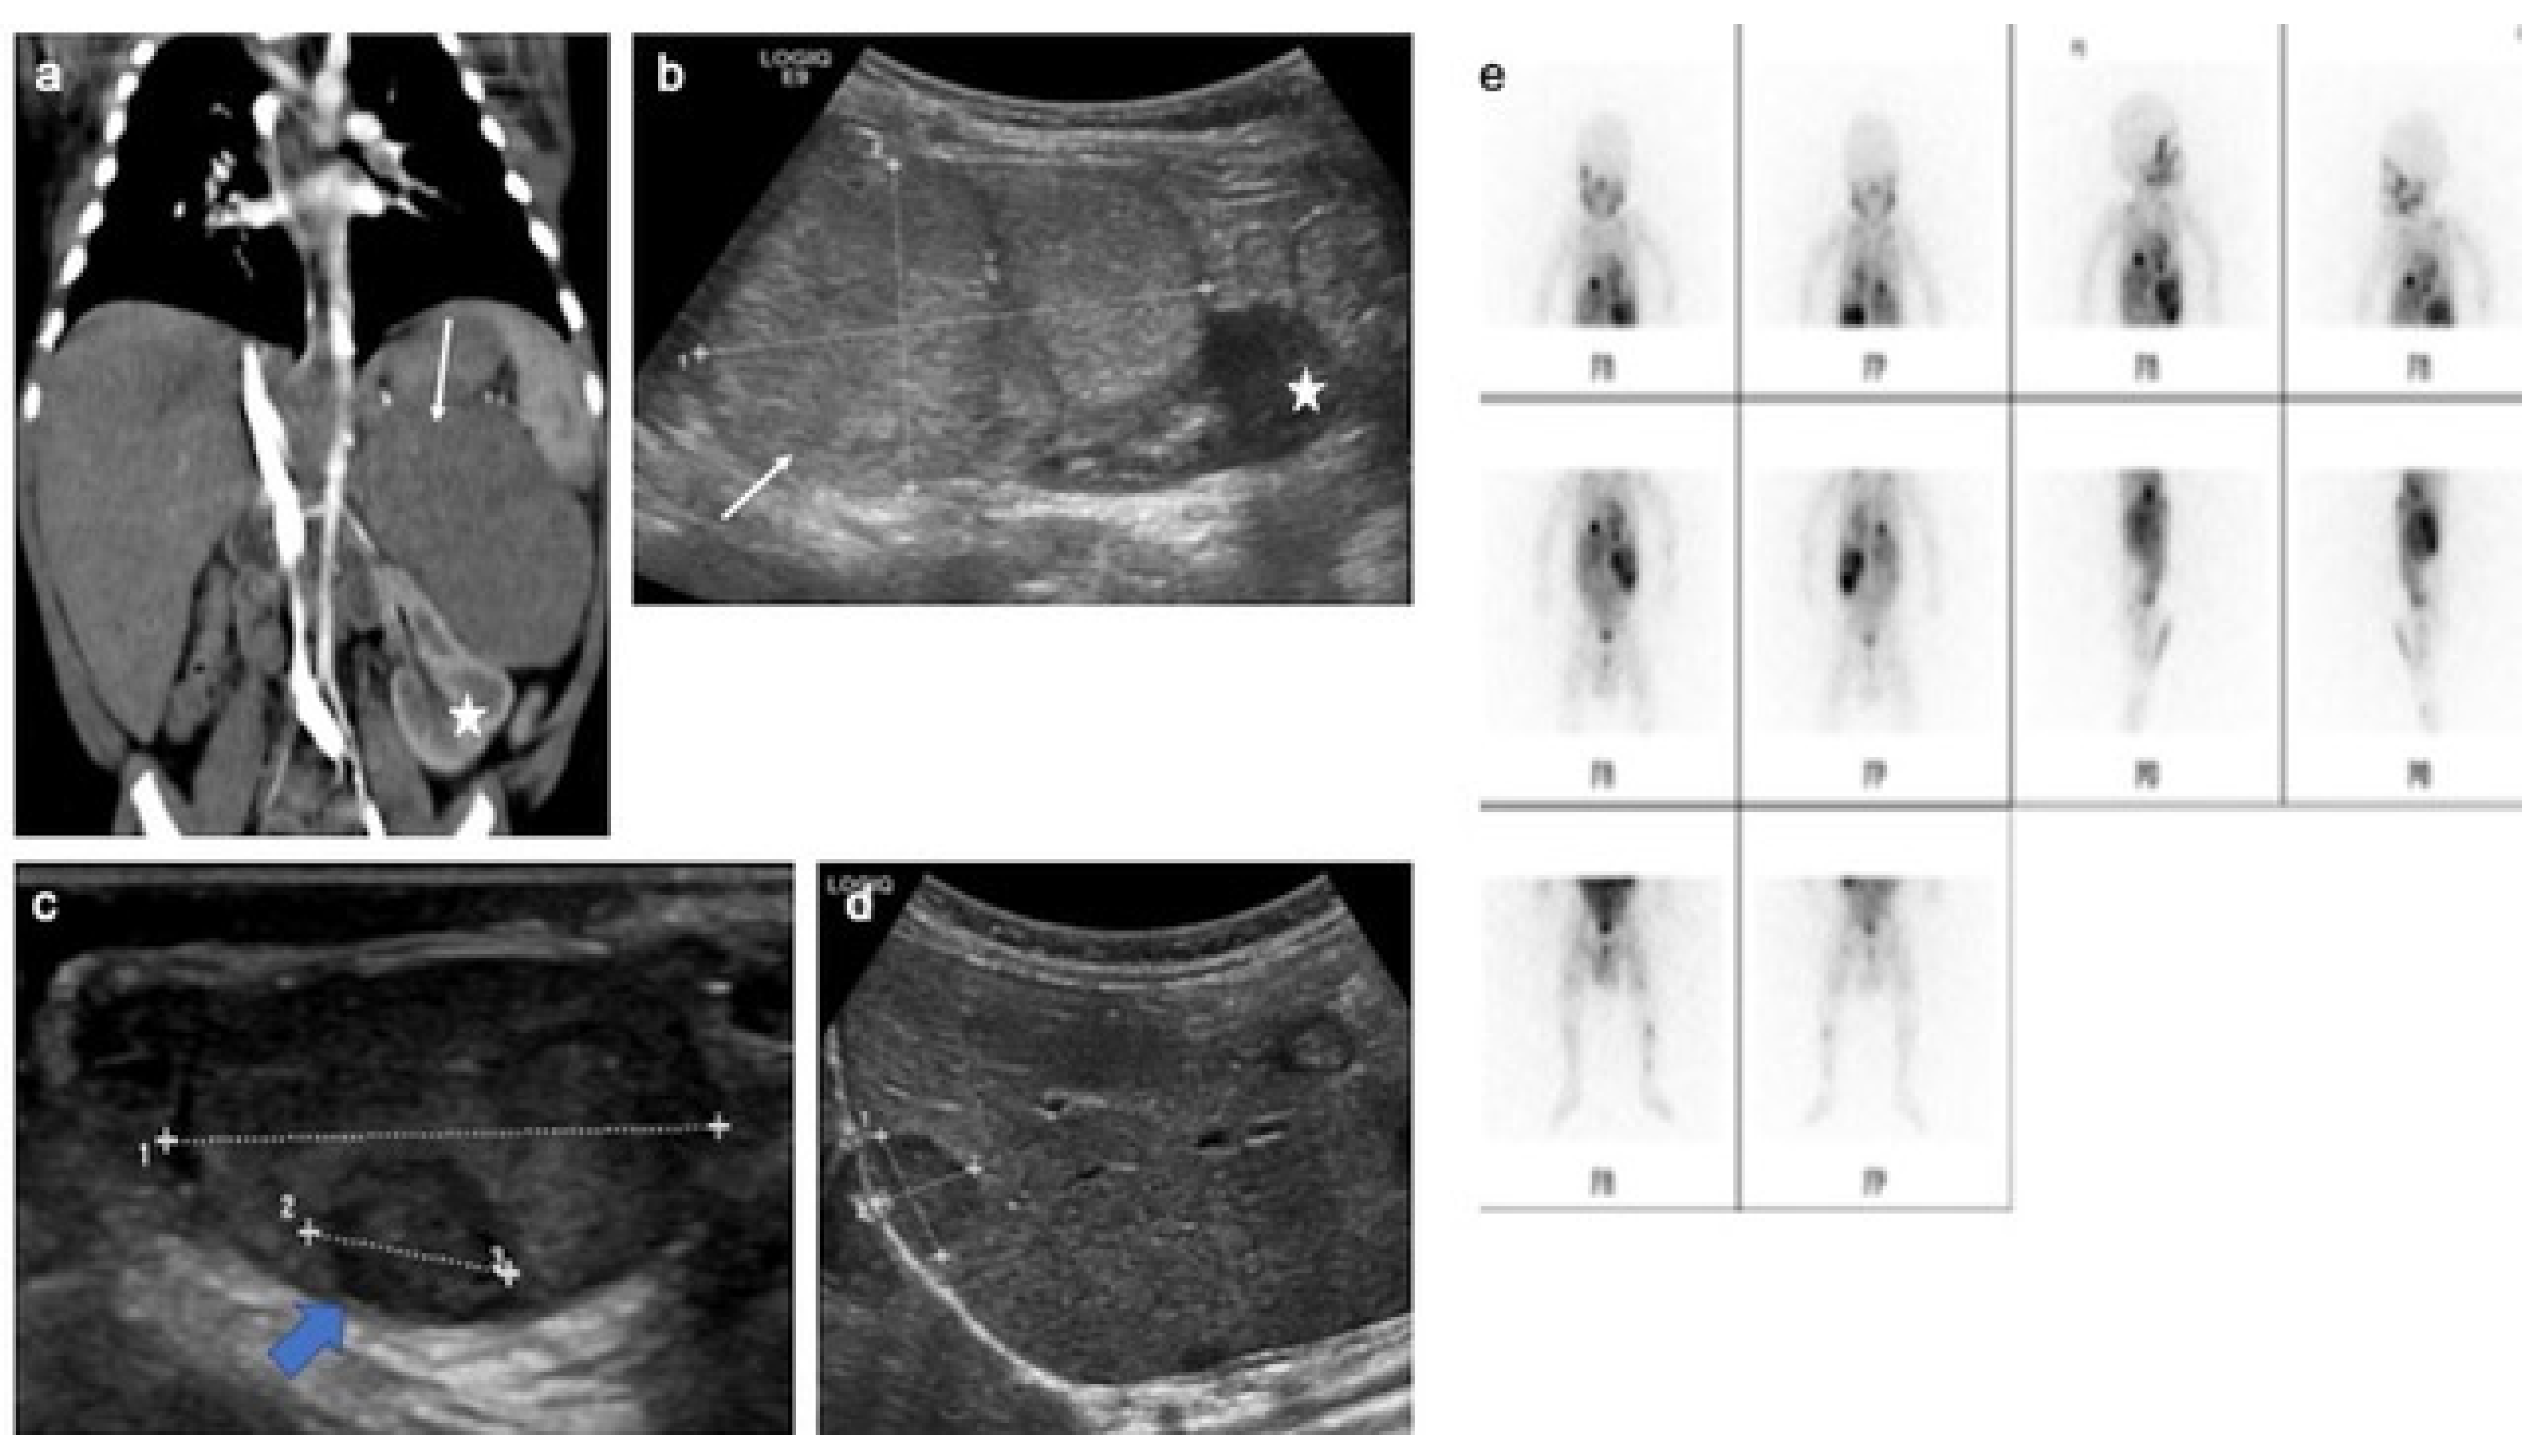

4.9. Testicular Adrenal Rest Tumors

- Yılmaz, R.; Şahin, D.; Aghayev, A.; Erol, O.B.; Poyrazoğlu, Ş.; Saka, N.; Yekeler, E. Sonography and Magnetic Resonance Imaging Characteristics of Testicular Adrenal Rest Tumors. Pol. J. Radiol. 2017, 82, 583–588. [Google Scholar] [CrossRef] [PubMed]

- Deshpande, S.S.; Shetty, D.; Saifi, S. Sonographic Appearance of Testicular Adrenal Rest Tumour in a Patient with Congenital Adrenal Hyperplasia. Pol. J. Radiol. 2017, 82, 526–529. [Google Scholar] [CrossRef] [PubMed]

- Mansoor, N.M.; Huang, D.Y.; Sidhu, P.S. Multiparametric ultrasound imaging characteristics of multiple testicular adrenal rest tumours in congenital adrenal hyperplasia. Ultrasound 2022, 30, 80–84. [Google Scholar] [CrossRef] [PubMed]